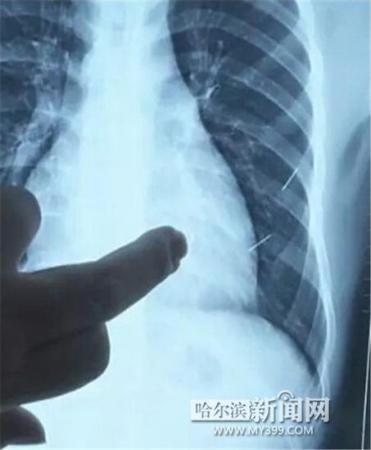

醫(yī)生指出X光片上的針狀物

昨日上午,記者在哈醫(yī)大二院第八住院部心外三病房找到了躺在病床上痛苦不堪的董立仁,家屬正在他身旁不斷安慰著他。見記者前來,董立仁母親李百燕拿出一張X光片,上面可以清晰地看到胸腔內(nèi)一共有4根針狀物,其中一根在心臟部位,兩根在胸腔壁上,還有一根在腹腔壁上。

心外三病房董立仁的主治醫(yī)生告訴記者,董立仁送到醫(yī)院時病情很危險,隨時可能危及生命?!巴ㄟ^檢查發(fā)現(xiàn),他心臟內(nèi)有一個金屬異物,正好在心臟上。心臟每次跳動都與其產(chǎn)生摩擦,導(dǎo)致出血,心包積液懷疑是血液。如果大量出血會凝結(jié)成血塊,血塊包裹住心臟就會影響心臟跳動,隨時都有停跳的危險。心臟上的異物是致命傷,其余胸腔壁和腹腔壁的異物傷害不大?!?/p>

昨天16時30分左右取針手術(shù)開始。因鋼針隨時會危及患者生命,此次手術(shù)定義為大型手術(shù)。開胸后,醫(yī)生打開董立仁心包,發(fā)現(xiàn)一枚鋼針已深深扎入心臟,僅露出1厘米長度在外。拔出鋼針后,醫(yī)生發(fā)現(xiàn),這枚針長達(dá)5厘米。受鋼針影響,心包出現(xiàn)大量積液,近800毫升。

隨后,在下胸壁位置,第二枚鋼針順利取出。在尋找另兩枚鋼針過程中,普外、胸外多名醫(yī)生也參與手術(shù),為主刀醫(yī)生提供更為穩(wěn)妥的處理建議。根據(jù)X光片顯示位置,醫(yī)生未在患者體內(nèi)找到剩余兩枚鋼針。醫(yī)生懷疑,其中一枚鋼針可能深藏在肋骨骨膜位置,無法尋找,最后決定結(jié)束手術(shù),做進(jìn)一步觀察,研究下一次手術(shù)方案。